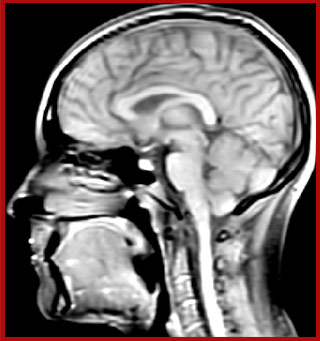

The techniques for measuring myelin have changed a lot over the years. “Since we are using the Elition, our myelin water images are much better. We're now acquiring 1 x 2 x 5 mm voxels and displaying at 1 x 1 x 2.5 mm. For a whole brain we can now measure the fraction of water in the myelin component in only about five or six minutes,” Dr. MacKay says.

of limiting MWI to the brain, even without the cerebellum, we can now spend about the same amount of time and scan the whole brain and the cervical spinal cord, which is a huge boost for us.” Dr. Rauscher says, “For MWI we perform 3D T2 with 32 or more echoes. This used to take a long time, but with Compressed SENSE we can decrease this to ten minutes for the whole head. Because of the large field of view (FOV) on the readout direction, we even get information from the brainstem, which we previously missed when we were using the GRASE approach. Having the whole head scan is nice because it has spatial resolution, orientation and FOV that are comparable to the standard 3D clinical MS scans, including the FLAIR and 3D T2, and a 3D T1 for brain volume.”

T1 - Weighted, Myelin Water Fraction Superimposed

Spinal cord coverage

Smaller, more isotropic voxels

Excellent detail in quantitative maps

Images courtesy of Adam Dvorak, Department of Physics and Astronomy, University of British Columbia